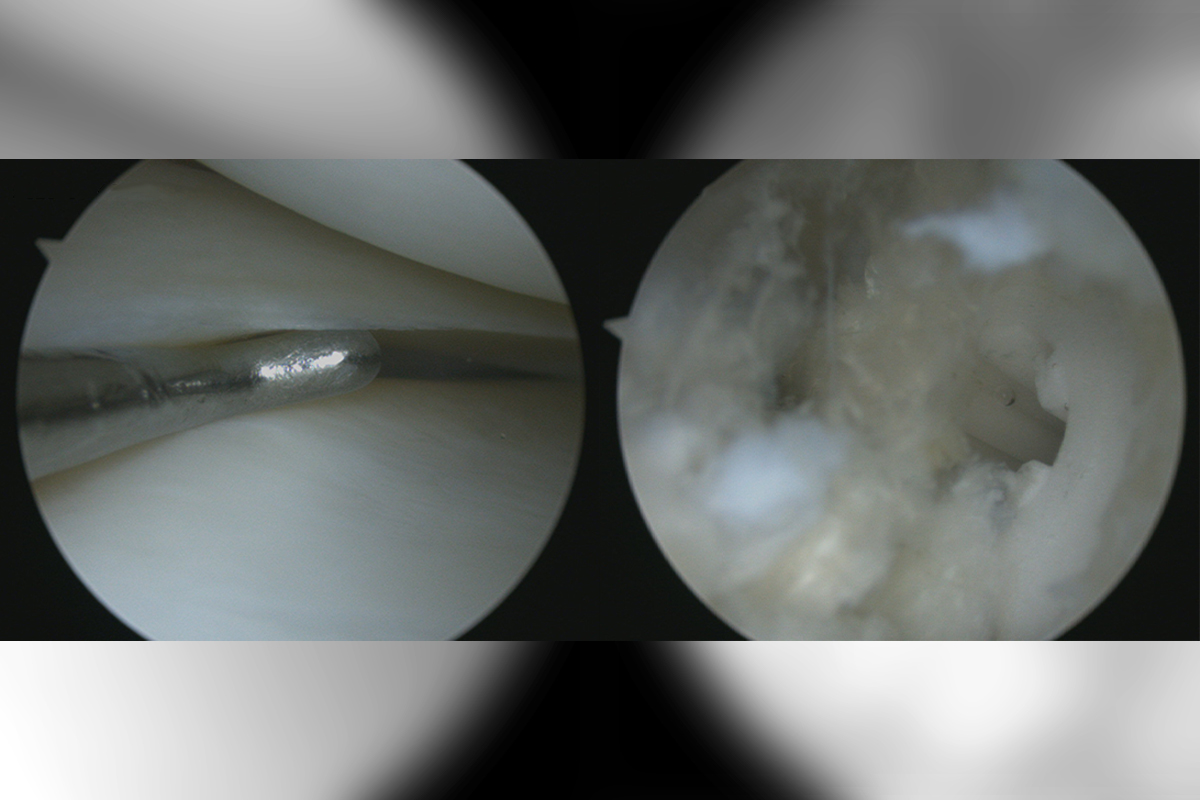

Sports Injuries

Sports Injuries can range from sprains and strains to fractures and concussions, often requiring medical attention and rehabilitation...